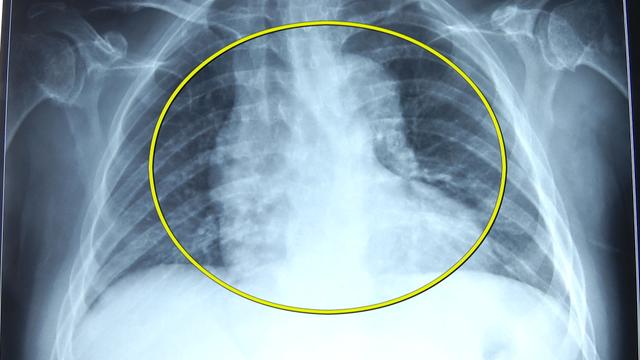

赵女士的手脚和脸型明显都偏大,记者用手对比以下,发现1米6的赵女士,不但手掌比记者的大,手指头也粗了许多。翻开赵女士以前的照片,对比后可以看到,赵女士的脸型也扩大了一圈。不仅如此,CT显示,赵女士的脏器也比常人大,你看这心脏都越过了脊柱,一部分都跑到了胸腔右侧。

南京军区总医院神经外科马驰原表示,赵女士内脏的脏器包括心脏,应该扩大了有正常人的20%,甚至以上。

专家解释,问题出在赵女士的大脑内,里面有一个叫脑垂体的东西,长了肿瘤,导致分泌出来的生长因子增多,刺激了赵女士的肢体和内脏变得粗壮肥大。别以为这病没啥大不了,其实还会致命:心脏肥大瓣膜闭合不严,容易造成心衰死亡。

马驰原医生表示,大部分病人是心衰原因导致死亡。寿命缩短,可以比正常预期的寿命缩短10年甚至20年。